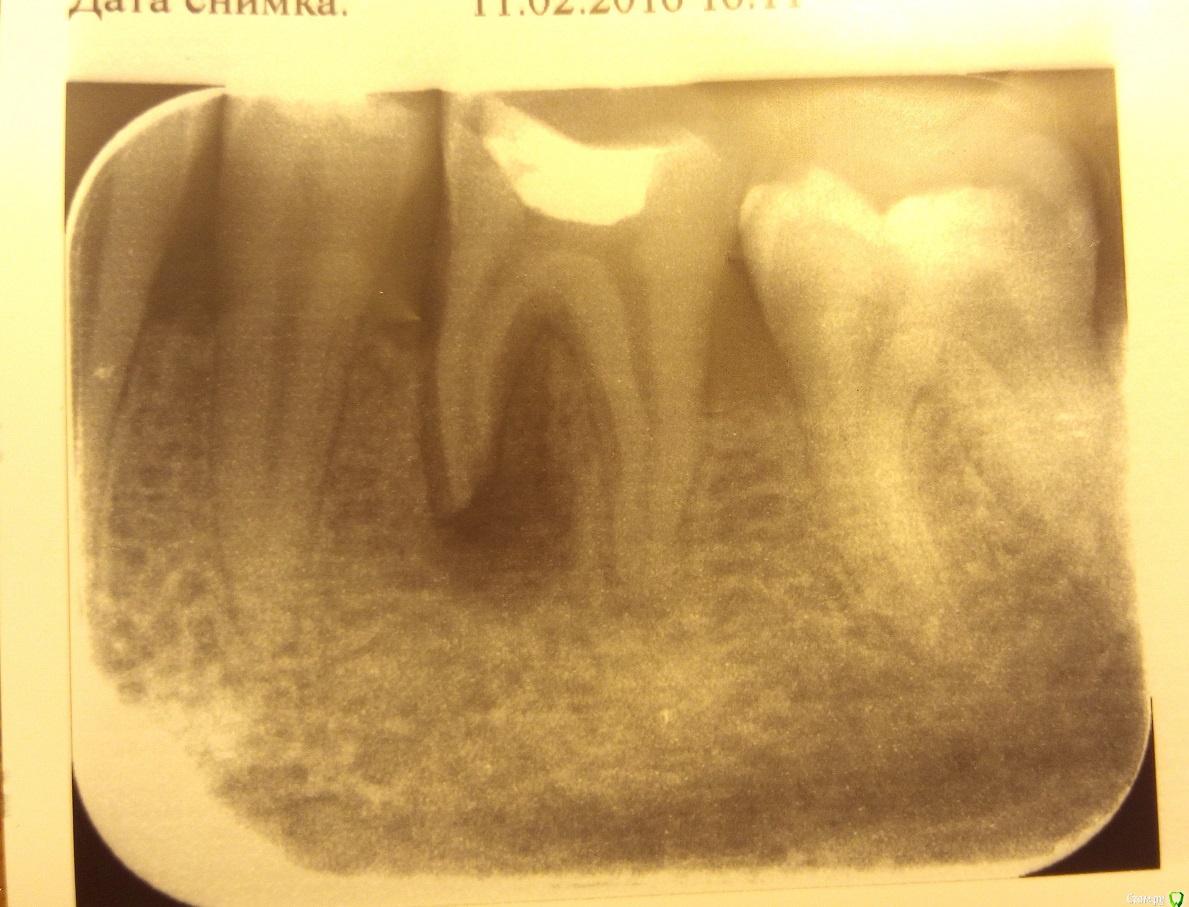

Jane251113 Опубликовано 11 февраля, 2016 Поделиться Опубликовано 11 февраля, 2016 (изменено) Добрый день! У мужа примерно полгода назад сильно болела десна в нижней части зуба и челюсть. Почувствовал давление, думал, что лезет зуб мудрости под ним. Сегодня сделал снимок, а там затемнение на корне и сам корень как будто разрушающийся. Мне кажется, что киста, но я не врач. Посмотрите, пожалуйста, что это может быть. Изменено 11 февраля, 2016 пользователем Jane251113 Ссылка на комментарий

shishok Опубликовано 11 февраля, 2016 Поделиться Опубликовано 11 февраля, 2016 В любом случае-это воспаление(киста или нет можно определить только гистологически).Зуб необходимо лечить. 2 Ссылка на комментарий

Jane251113 Опубликовано 12 февраля, 2016 Автор Поделиться Опубликовано 12 февраля, 2016 В любом случае-это воспаление(киста или нет можно определить только гистологически).Зуб необходимо лечить.Спасибо за ответ. Сегодня зуб пришлось удалить(( Ссылка на комментарий

Jane251113 Опубликовано 12 февраля, 2016 Автор Поделиться Опубликовано 12 февраля, 2016 (изменено) Почему? По показаниям. Воспаление кисты пошло, хирург сказал, что без вариантов Изменено 12 февраля, 2016 пользователем Jane251113 Ссылка на комментарий